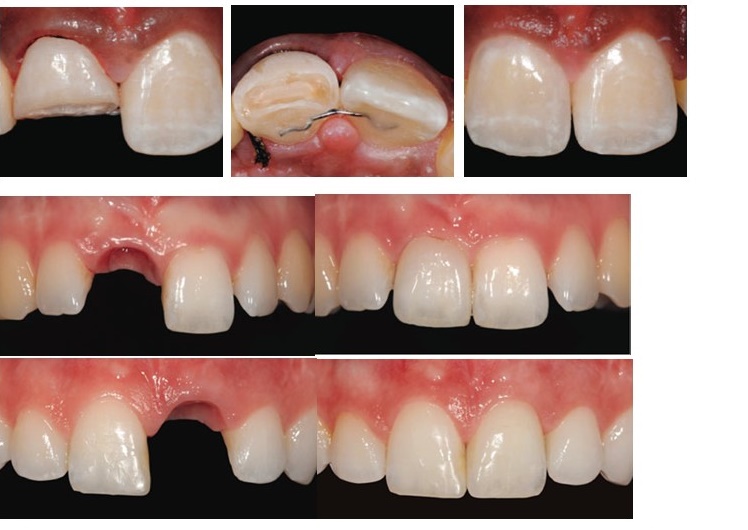

VINCENT FEHMER (MDT) KLINIKINIAI ATVEJAI: